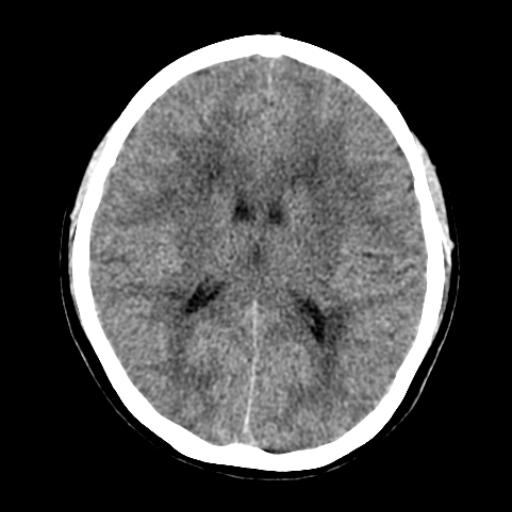

40f头晕十多天,右上肢麻木一天

脑白质变性或ms

脑白质脱髓鞘改变。

脑白质病;建议行mri检查。